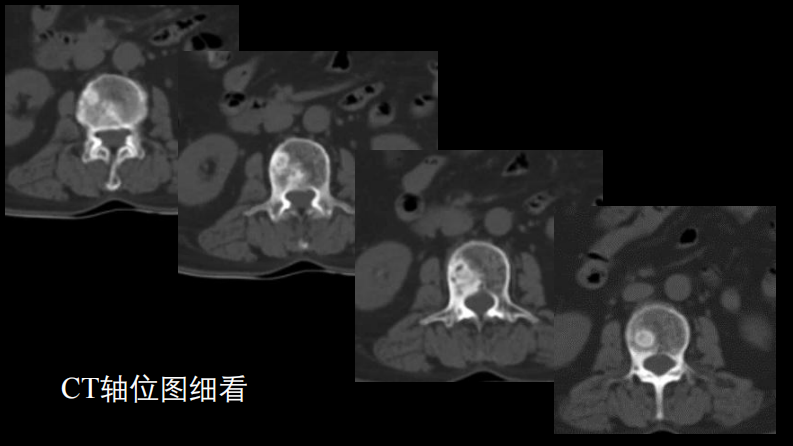

一例椎体的局灶病变影像表现分析暨影像诊断扩展.pdf